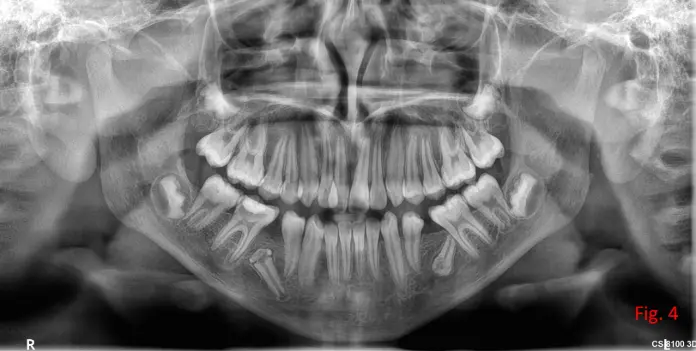

Estudio solicitado: Radiografía panorámica inicial.

Durante la práctica se observa la presencia de ambos caninos inferiores retenidos. (RX panorámica)

Ambas piezas presentan adaptaciones morfológicas compatibles con modificaciones ocurridas durante la odontogénesis, probablemente condicionadas por el espacio óseo disponible y las presiones locales. (Fig. 4)